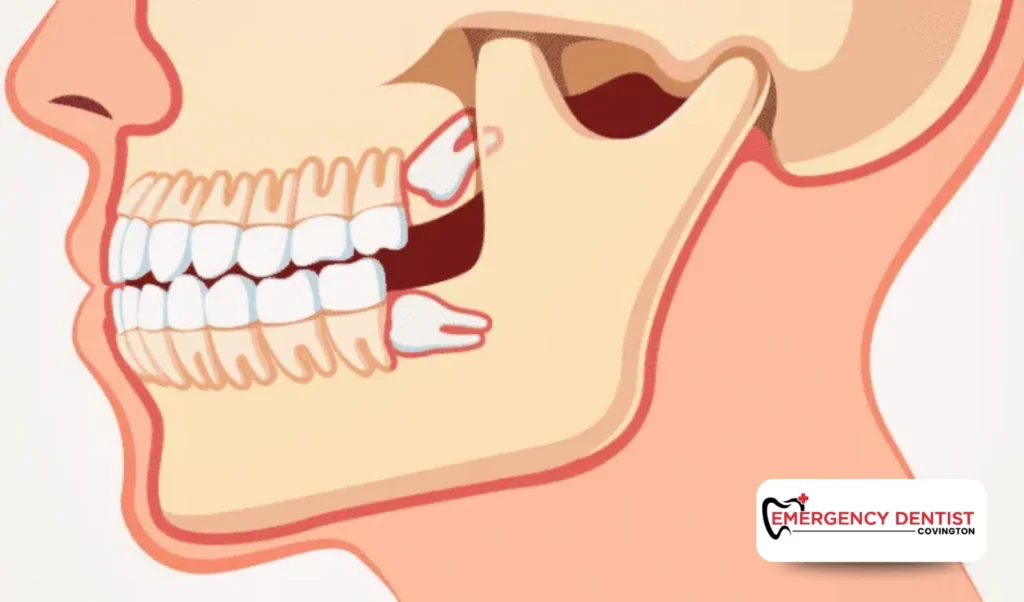

How an Impacted Wisdom Tooth Affects Cost

An impacted wisdom tooth does not fully come through the gums. It may grow sideways or push against neighboring teeth. These situations often require oral surgery.

Why Early Removal Supports Oral Health

Wisdom teeth can be difficult to clean, especially if they are partially erupted. Over time, trapped bacteria may lead to infection and gum irritation.

Delaying removal may result in:

- Increased swelling

- More complex dental care

- Higher overall tooth extraction cost

Addressing concerns early can prevent more serious dental procedures in the future.